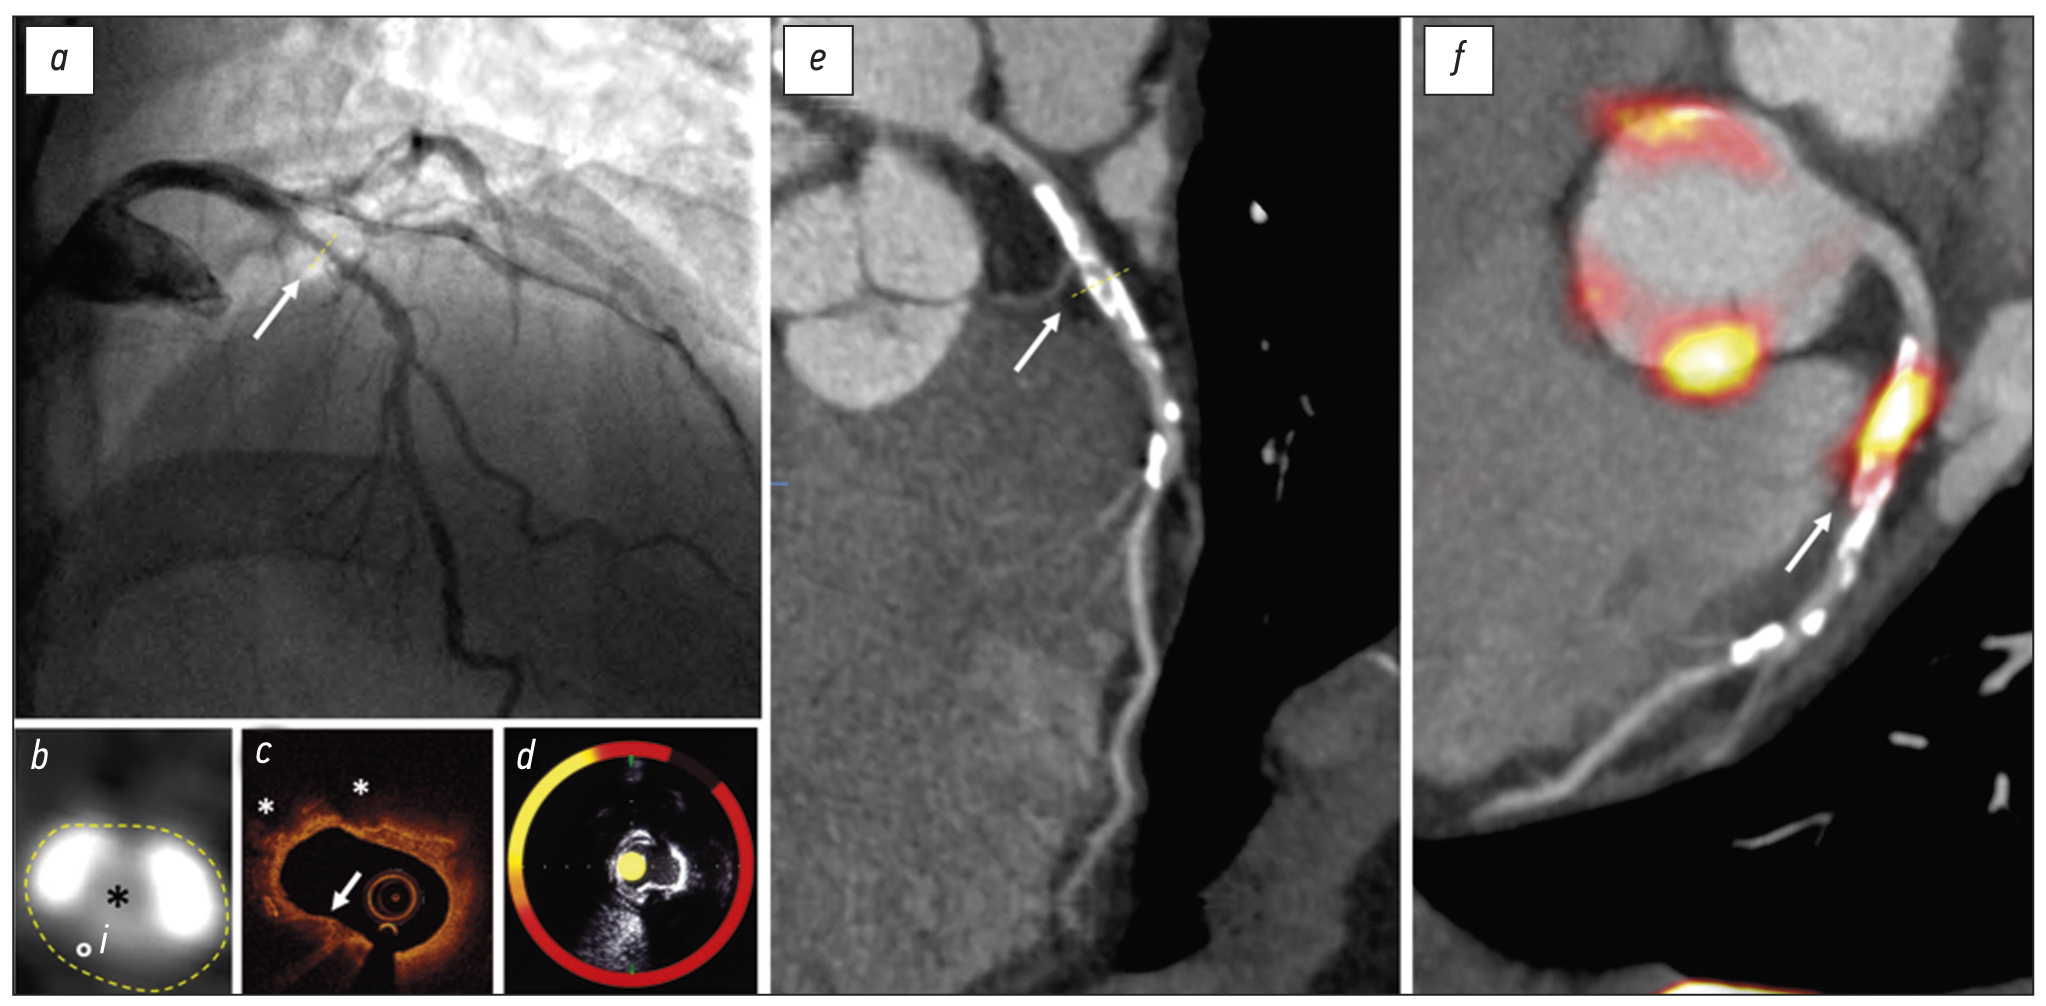

Fig. 2. Imaging of coronary atherosclerosis in a patient with myocardial infarction without ST segment elevation.

(A) Catheter angiography shows an irregular lesion in the proximal left anterior descending coronary artery (artery). (B) Transaxial view of the coronary lesion on CT (i) shows a complex plaque with calcified (white) and fibrofatty (°) plaque around a central lumen (*). (C) Optical coherence tomography detects a thin fibrous cap (arrow) and lipid pools (*). (D) Combined near infrared spectroscopy and intravascular ultrasound confirms high lipid burden within the plaque (yellow). (E) Centreline reconstruction of the left anterior descending artery visualizes calcification and plaque formation throughout the entire vessel. (F) 18F-Sodium fluoride positron emission tomography/ CT detects high uptake in the atherosclerotic plaque

Near infrared spectroscopy/intravascular ultrasound

Near infrared spectroscopy (NIRS) is another catheter-based invasive technique. NIRS does not require a blood free field and uses wave scatter to produce a gradient map corresponding to the probability of adjacent lipid (Figure 2D). The resultant lipid-core burden index (LCBI) describes the ratio of high lipid content in adjacent structures against the total study area. Modern probes are combined with intravascular ultrasound (IVUS) to provide structural context to the morphological data.21

IVUS is a more established and, consequently, cost-effective technique than OCT and NIRS. It packages a high-frequency ultrasound probe in a catheter that can directly visualize adjacent atherosclerotic plaque from within the lumen (Figure 2D). High-resolution greyscale images show the structure of atherosclerotic plaque and the adjacent vessel wall. Features of plaque components can be identified by analyzing the backscatter and can reliably reveal the lipid-rich necrotic core, calcification and fibrofatty plaque.22,23 Despite reasonable tissue penetration, IVUS lacks the spatial resolution to measure the thickness of the fibrous cap. Like conventional ultrasound, mineralized calcium deposits cast acoustic shadows, thereby obscuring underlying tissue detail.

18F-Sodium fluoride (18F-NaF) binds to exposed hydroxyapatite crystals. Due to surface area effects, it preferentially binds to areas of developing microcalcification, which is beyond the resolution of CT.63,68 Because 18F-NaF is not taken up by myocardium, the background signal is low, which allows even relatively low signal to be visualized within the coronary vessels (Figure 2)—a significant advantage over 18F-FDG.